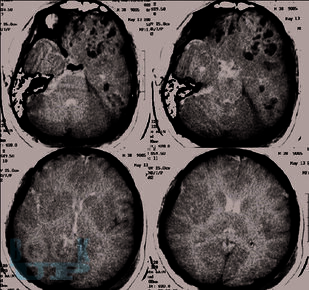

В этой книге мы рассказываем о динамике и взаимосвязи патологических процессов. Эти знания позволяют обосновать вашу тактику. В книге обсуждаются взаимосвязь первичного и вторичного повреждения мозга. Как внутричерепная гипертензия приводит к дислокациям и вклинениям головного мозга и/или нарушениям кровоснабжения мозга. Обсуждается регуляция тонуса сосудов мозга в норме и патологии. Зависимость церебрального перфузионного давления от среднего артериального давления, внутричерепного давления и сохранности ауторегуляции тонуса мозговых сосудов. Рассматриваем варианты отека мозга и возможности лечения. Мы рассказываем как на основе результатов мониторинга внутричерепного давления принимаются решения о том как лечить пациента.